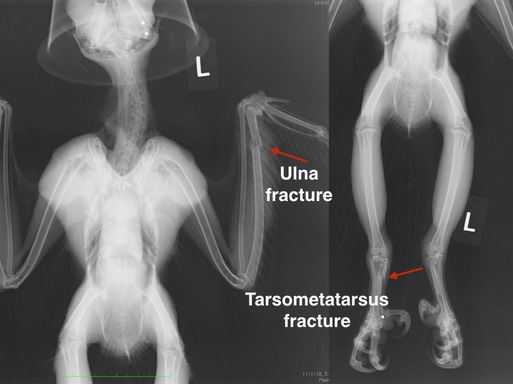

Great Horned Owl 18-693

Volunteer Marla captured Great Horned Owl 18-693 along a Pasco freeway with traffic zipping by at 70 miles an hour. The young owl had obviously figured out how to catch prey. She weighed 1560 grams - 1200 is a normal weight for a female. Unfortunately, she had not learned to avoid vehicles. An exam found both a broken wing and a broken leg. Radiographs also showed that the owl had been shot some time earlier. Can you find all three pellets?